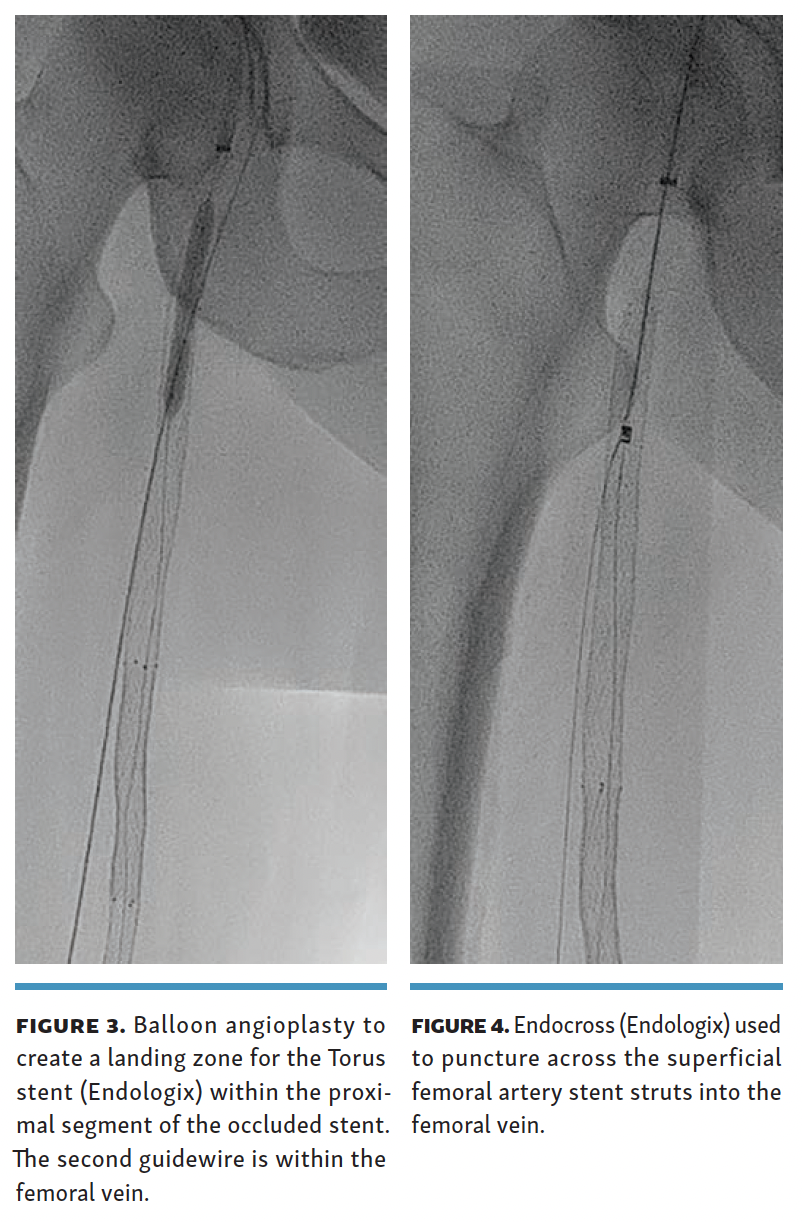

A 0.014-inch Glidewire Advantage Track wire (Terumo) was used to reenter the occluded SFA stent with the help of a Quick-Cross support catheter (Philips), followed by a 4-mm balloon angioplasty of the occluded proximal SFA stent (Figure 3). The Endocross device was then placed in the recanalized proximal SFA stent, and needle entry was obtained into the femoral vein through the stent struts (Figure 4) 5 cm below the proximal end of the occluded SFA stent.